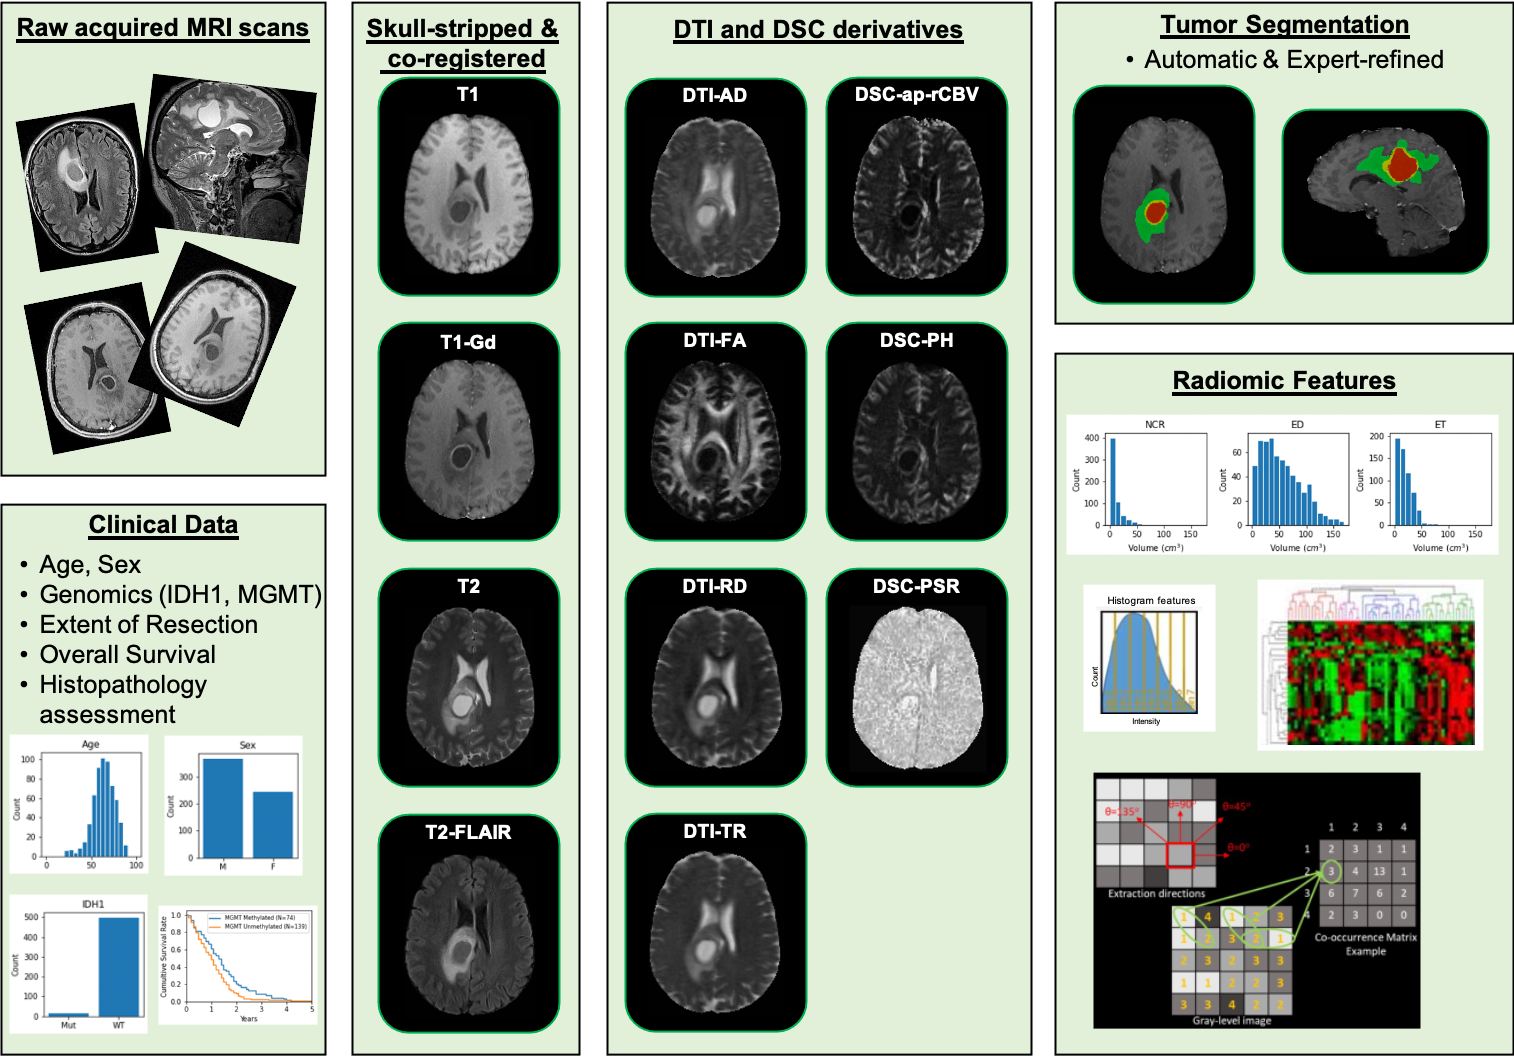

该数据集包含来自宾夕法尼亚大学的胶质母细胞瘤(GBM)患者的多参数磁共振成像(mpMRI)扫描,结合患者的人口统计信息、临床结果(例如,总生存期、基因组信息、肿瘤进展),以及多个组织学上不同的肿瘤亚区域的计算机辅助和手动修正的分割标签、整个大脑的计算机辅助和手动修正的分割、丰富的放射组学特征以及其对应的NIfTI格式。数据为DICOM格式,3D数据,颅骨在原始DICOM数据中保留,没有去除。每个病人的数据中包含了T1加权,T2加权,T1加权对比度增强和T2 FLAIR四种图像数据。有些病人的四种数据并不完整,缺失部分数据。T1加权3D数据大约300左右,T2加权数据大约100左右,T2-FLAIR 数据大约100个。

数据样本可视化